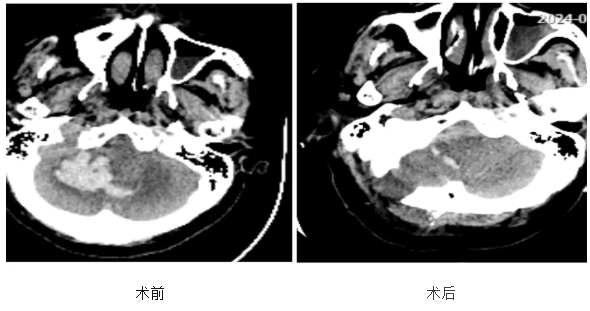

8月19日凌晨四点,75岁的李奶奶(化姓)因突发恶心、呕吐伴意识不清,被紧急送往湖北省第三人民医院(省中山医院)阳逻院区神经外科重症监护室。急诊头颅CT提示小脑出血量约20ml。小脑位于后颅窝,手术空间狭小,血肿压迫脑干随时可能出现呼吸心跳骤停。神经外科主任李俊、副主任林爱龙立即召开两院区线上视频会议讨论手术方案,因李奶奶病情凶险,手术是唯一可能挽救生命的方式。林爱龙副主任与家属沟通后,家属表示:“只要有一线希望,就全力抢救。”时间就是生命,伤情就是命令!得到家属的全力支持后,林爱龙副主任和别毕洲副主任立即为李奶奶实施神经内镜下小脑血肿清除术,经过2小时的连续奋战,手术顺利完成。

术后,在神外NICU医护人员的精心治疗下,李奶奶各项生命体征逐渐平稳。术后头颅CT显示患者脑部血肿基本清除。医护团队也不由得松了一口气。经过两周多的精心护理,李奶奶顺利康复出院。